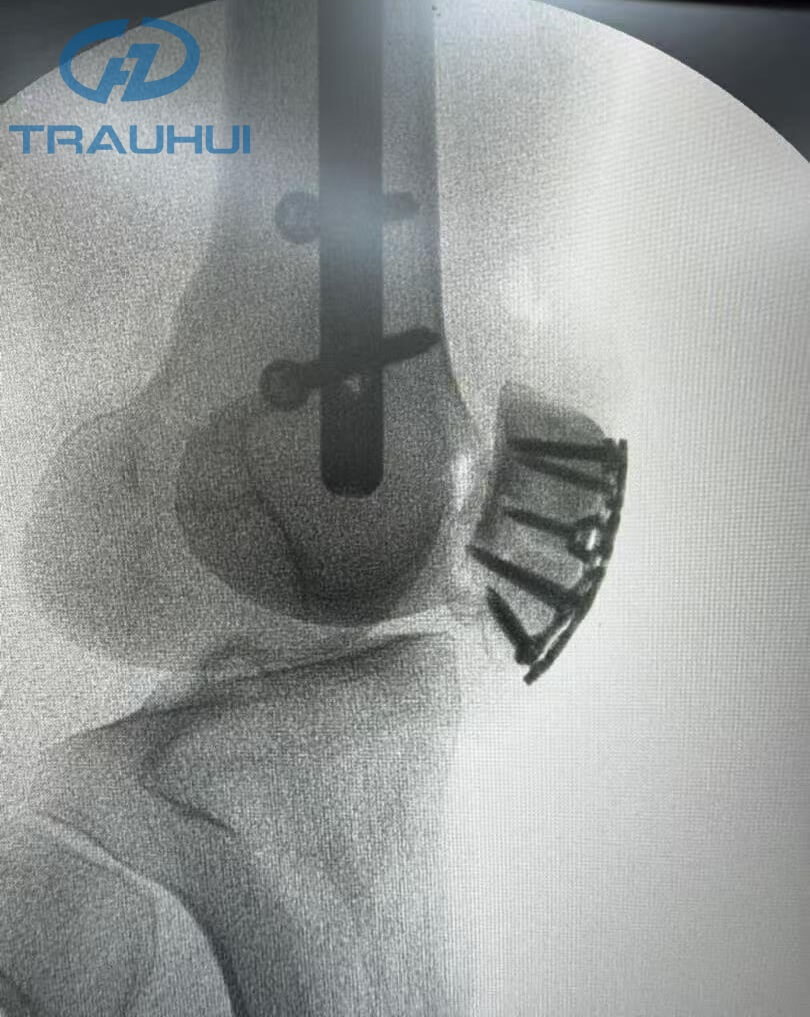

Anterior Patella Plates4.jpg

Figure 5: X-Ray

The post-surgery X-ray confirmed what the surgeon felt in the OR: unmatched stability. By replacing the "settling" nature of cerclage wires with the rigid, anatomical fixation of our new plate, the patient is now positioned for a faster rehabilitation with a reduced risk of hardware failure.